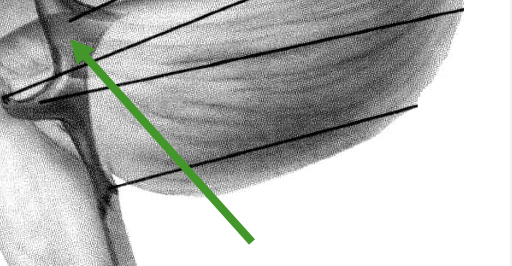

anterior median fissure

pyramid decussation

pyramid

olivary eminence

preolivary sulcus

postolivary sulcus

medulla (ventral features)